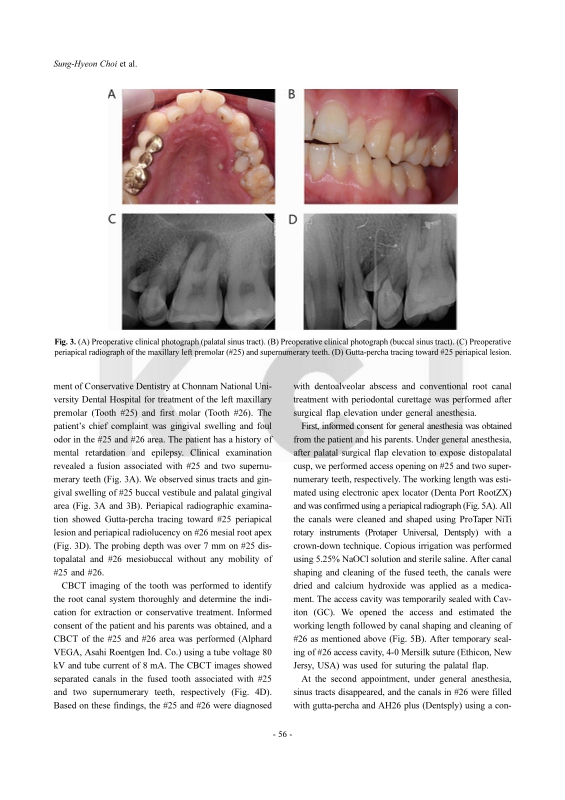

The aim of this study is to describe the endodontic treatment of a radix entomolaris (RE) with the C-shaped canal in mandibular first molar and a fused maxillary premolar with two supernumerary teeth with the separated root canal using cone-beam computed tomography imaging (CBCT). In our cases, non-surgical endodontic treatment based on the results of CBCT diagnosis, ProTaper rotary system, hand instrumentation, and passive ultrasonic irrigation along with periodontal treatment resulted in long-term and successful prognosis. Therefore, CBCT analysis an effective diagnostic tool for the treatment of teeth containing complex root canals.

Endodontic treatment of tooth with morphological anomalies using cone-beam computed tomography Sung-Hyeon Choi, Na-Kyung Yoon, Ji-Hyun Jang, Young-Hoon Kim, Hoon-Sang Chang, Yun-Chan Hwang, In-Nam Hwang, Won-Mann Oh, Bin-Na Lee pp.53-61